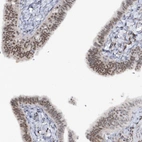

Immunohistochemical staining of human testis shows strong nuclear positivity in Leydig cells.